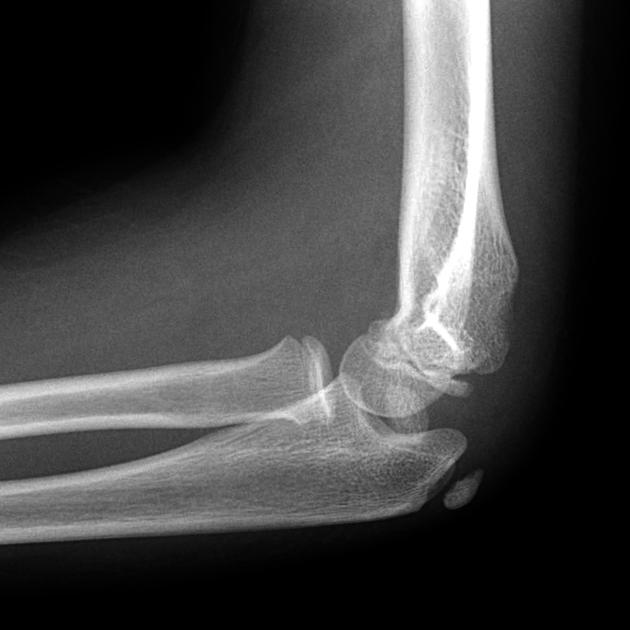

Example 3

Diagnosis

Ulnar shaft fracture